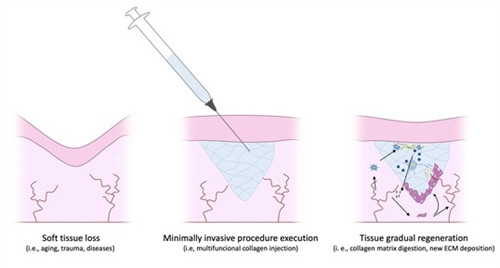

我发现,他们在这方面确实有独到之处:普遍采用高清3D内窥镜、超声波引导等精密设备,手术视野放大数十倍,能清晰分辨奥美定与正常组织的边界;手术入路设计巧妙,多选择发际线内、口腔黏膜等隐蔽位置,力求无痕;更重要的是,他们强调“分层分次、精细剥离”的理念,不是粗暴刮除,而是在保护血管、神经和正常脂肪组织的前提下,像考古一样一点点将侵蚀的奥美定分离出来。

了解不同技术路径的优劣(如传统刮除 vs. 内窥镜精细剥离),查看真实的、未经修饰的术前术后对比病例(尤其是影像学证据),了解医生的正规背景和主攻方向,这些至关重要。